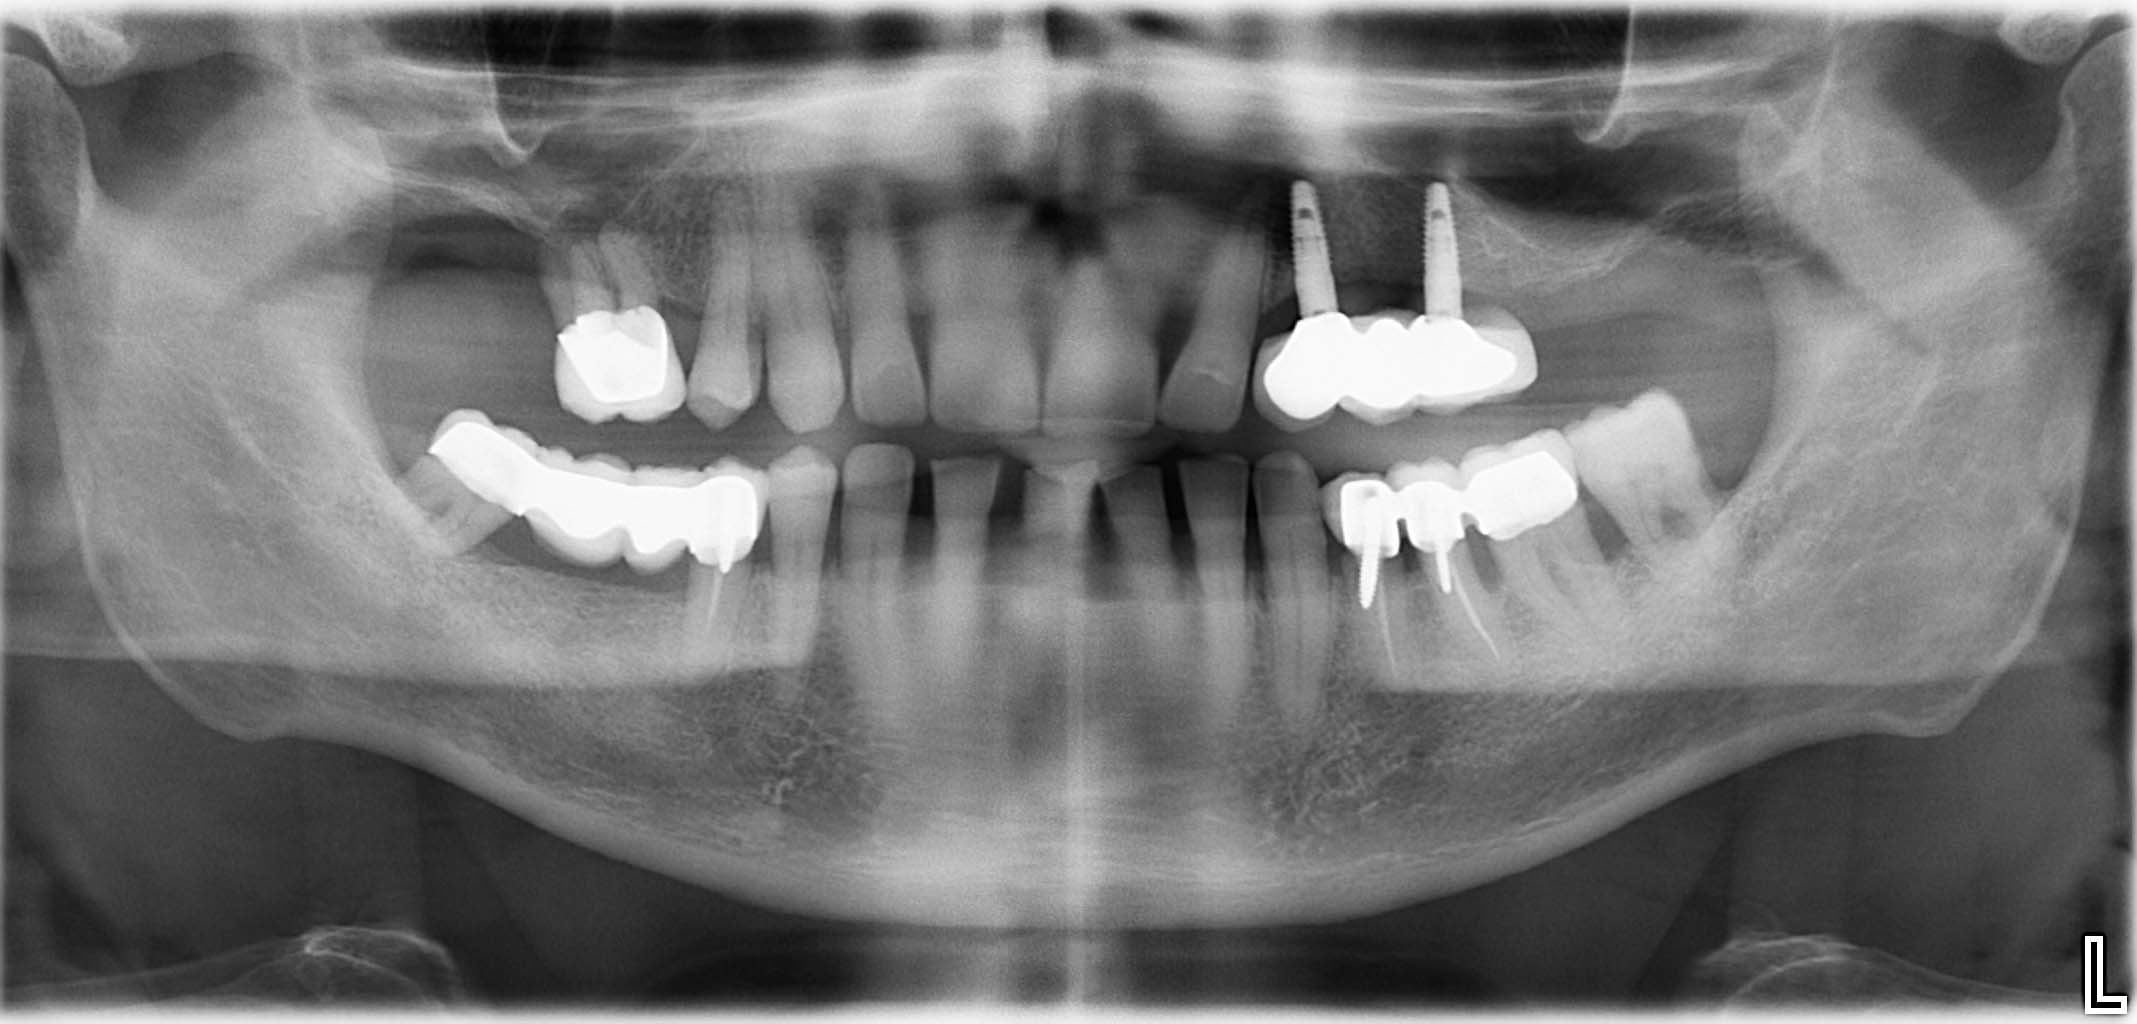

Erfolgreich implantierte Patientenfälle (klinische Fotos)